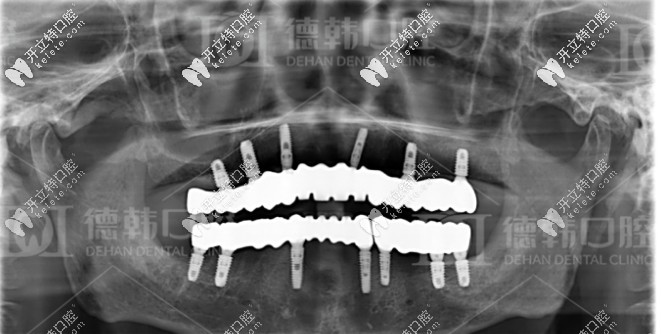

張?jiān)洪L針對爺爺年齡大、口腔條件不佳的情況,為其制定了一套即拔即種的全口種植方案:總共種植了13顆種植體,其中下頜種植7顆種植體,十五天后再種植上半口,上頜種植了6顆種植體。

經(jīng)過種植體埋入、放置基臺(tái)及裝牙冠等流程,一共花費(fèi)了6個(gè)月,爺爺終于恢復(fù)了滿口牙。

種牙成功后的牙片